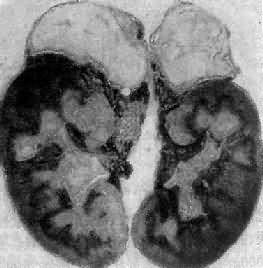

引起本病的病因主要有双侧肾上腺结核(图15-15)和特发性肾上腺萎缩,偶尔也可因转移癌引起。特发性肾上腺萎缩(idiopathic adrenal atrophy)是自家免疫性炎症,故又称自家免疫性肾上腺炎(autoimmue adrenalitis),多见于青年,女性显著多于男性。病人血中常有抗肾上腺皮质细胞线粒体或微粒体抗体,常与其他自家免疫性疾病合并。双侧肾上腺高度萎缩,共重2.5g以下;皮质菲薄,镜下除皮质萎缩外,有大量淋巴细胞和浆细胞浸润。

图15-15 双侧肾上腺结核